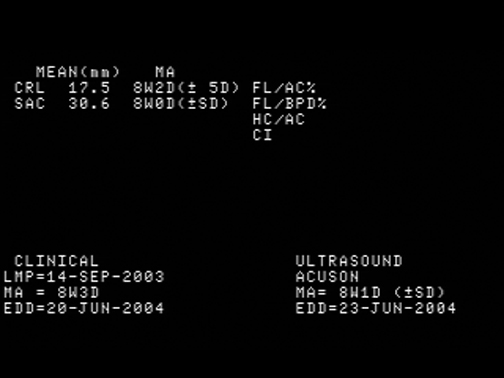

Crown Rump Length (CRL) |

Measurements |